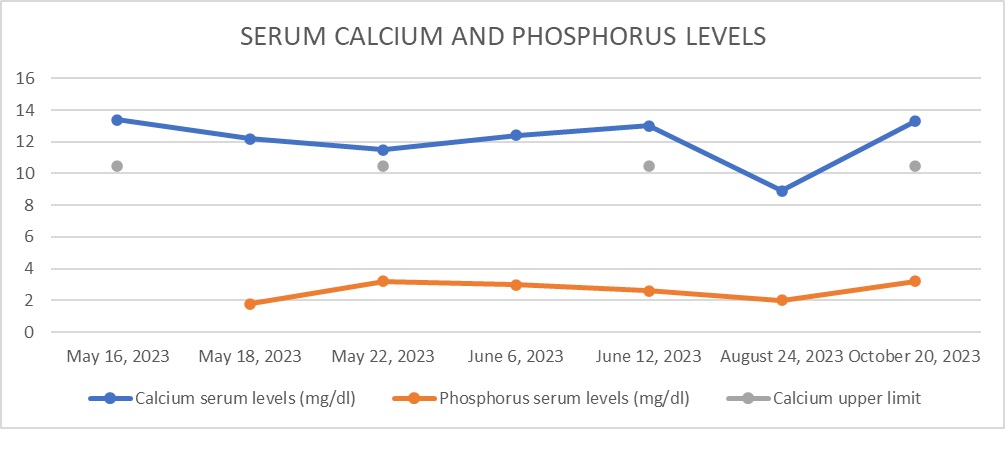

Case Presentation: A 44-year-old African American male with a medical history of human immunodeficiency virus (HIV) and chronic kidney disease (CKD) presented to the hospital with nonspecific complaints, including flank pain. Initial laboratory tests and imaging studies confirmed a diagnosis of nephrolithiasis and acute kidney injury with concomitant hypercalcemia. The patient was hospitalized and treated with intravenous fluids and pamidronate, which led to the normalization of calcium levels. Further investigation of the hypercalcemia revealed an inappropriately normal parathyroid hormone (PTH) level for the degree of calcium elevation. Additional diagnostic workup, including a computed tomography (CT) scan, revealed hyperlucent deposits in both gluteal regions. Upon questioning, the patient revealed a history of silicone injections administered 20 years earlier, raising the suspicion of exogenous overproduction of 1,25-dihydroxyvitamin D. Following treatment, his calcium levels improved, and he was advised to continue outpatient follow-up. However, one month later, he was readmitted with recurrent hypercalcemia. Due to the complexity of managing hypercalcemia in the context of CKD, the nephrology team recommended initiating denosumab, as bisphosphonates are not an appropriate medication in patients with impaired renal function. After receiving the first dose, the patient’s calcium levels improved; however, he was lost to follow-up before the second dose could be administered.

Discussion: Silicone is known to be a rare cause of hypercalcemia, often years after its administration as part of cosmetic procedures. In 1964, Winer et al. described three biopsy-proven cases of granuloma formation after silicone injection, naming them “siliconomas” [1]. They observed siliconomas with a polarized microscope, noting the presence of crystals in the tissue. This constitutes the initial evidence of silicone’s role in causing this phenomenon. The exact mechanism of this granulomatous response is not completely understood but is thought to be similar to what happens in sarcoidosis-induced granulomas [2, 3]. A recent systematic review in 2018 by Tachamo et al. described 23 cases of patients (mostly female) who had received silicone, polymethylmethacrylate, or paraffin oil, and years later developed hypercalcemia [4]. Diagnostic tools like CT scans or PET fluorodeoxyglucose (FDG) are useful in the evaluation of granulomatous diseases like sarcoidosis or amyloidosis and in the diagnostic and prognostic evaluation of malignancies [5]. Currently, there is no definitive treatment for silicone-induced hypercalcemia. Many available case reports [1, 4, 6-11] used strategies like hydration, bisphosphonates, and systemic steroids as the most common management. In our patient, due to his chronic kidney disease, bisphosphonates were not an appropriate first-line therapy, and for this reason, the managing endocrinologist considered denosumab for his outpatient therapy.